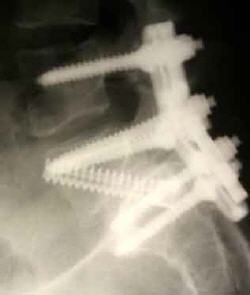

Stabilisierung der Wirbelsäule mit einem Schrauben-Stab-System: Die Bandscheibe hält die Wirbelsäule aufrecht. Im Laufe der Jahre entstehen in der Bandscheibe häufig Risse. Auch Verletzungen oder Tumore können die Bandscheiben zerstören. Eine operative Stabilisierung ist notwendig.